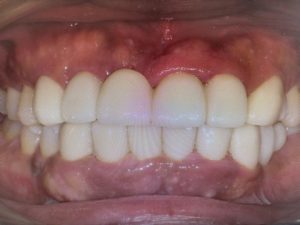

その後、挙上量はシーラシステムを利用して計測し、本来のかみ合わせの位置を再現出来るように技工士さんと相談して本歯を作ってもらいました。

前歯ももちろん審美的に整えて、治療期間は1.5ヶ月でした。

患者様のご理解もあって治療はスムーズに進み、仕上がりにも大変満足していただきました。